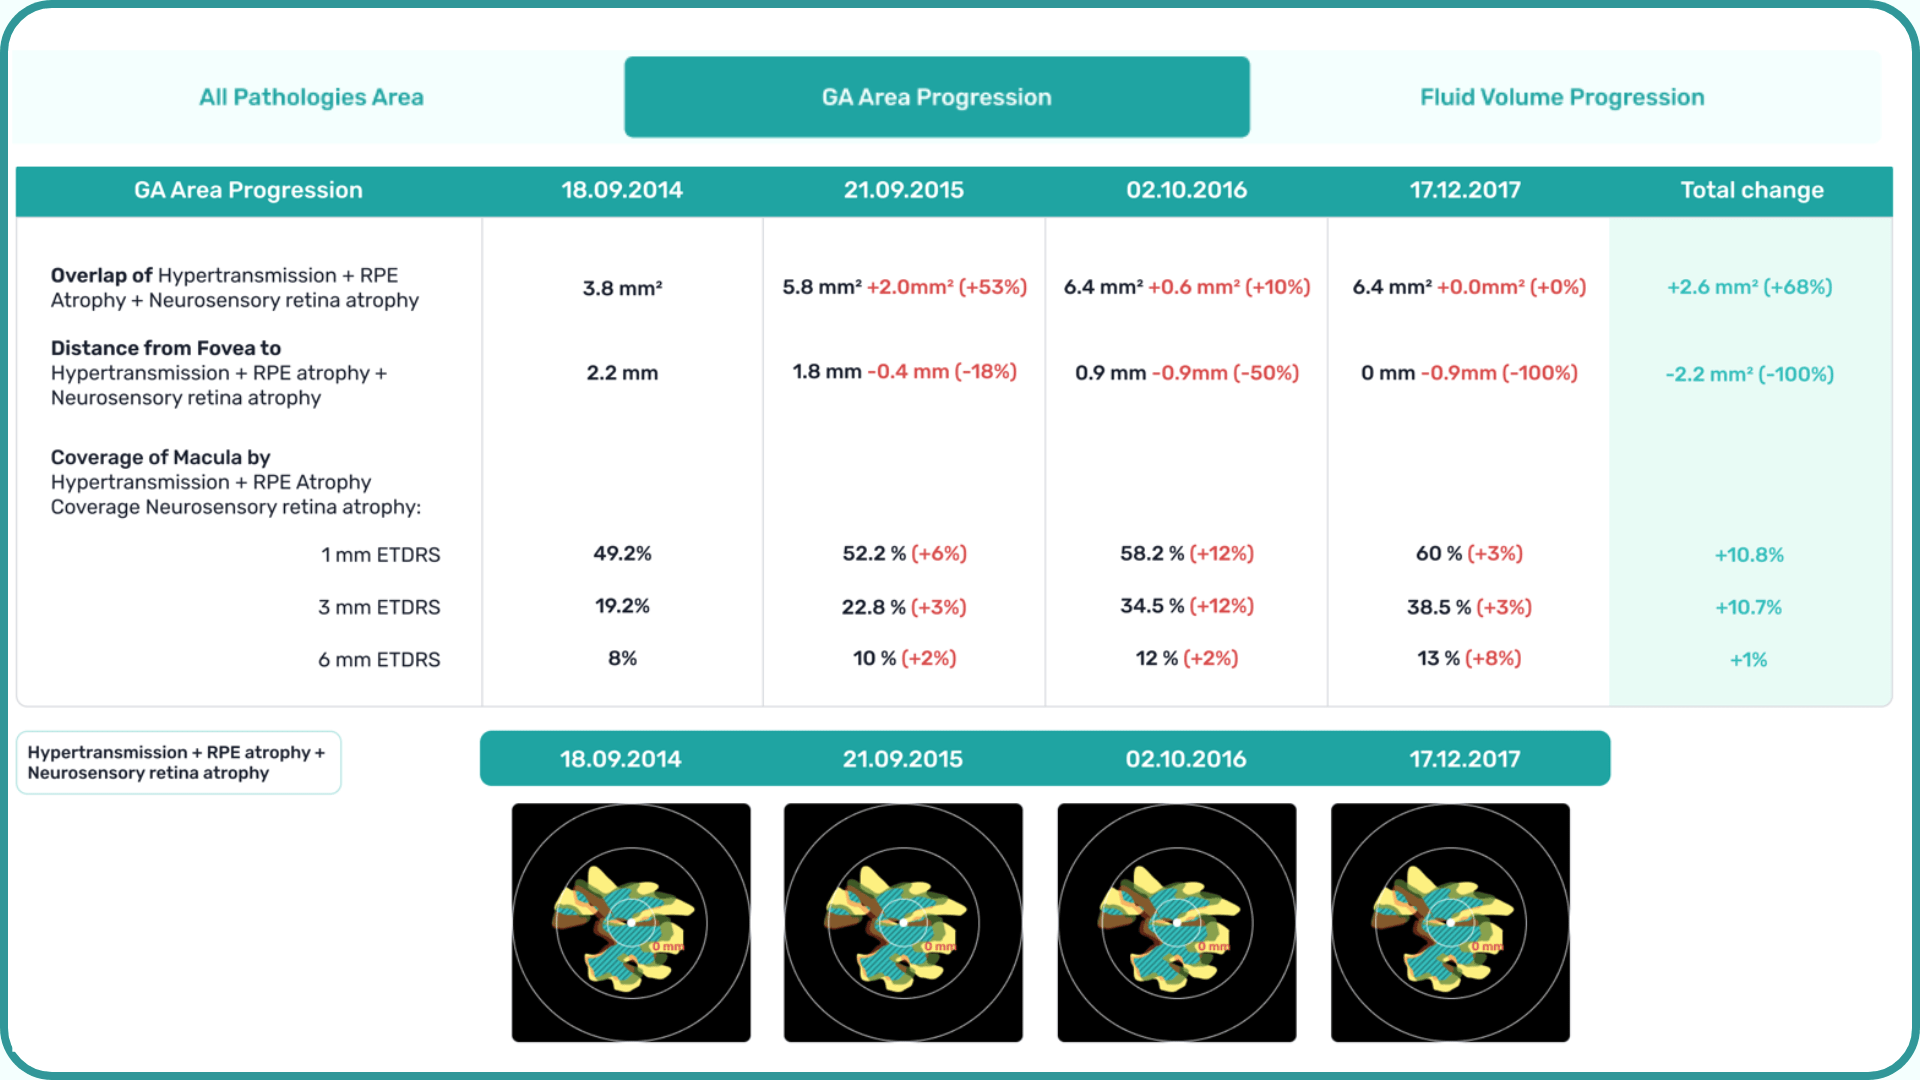

AI-assisted readings of OCT scans are already helping not only with pathology detection but also with the analysis of its progression or response to treatment. This represents a new approach to monitoring, where practitioners no longer need to sift through various patient notes but can directly compare reports from previous examinations and observe how, for instance, shadowing has changed in micrometers.

Measuring treatment progress: biomarkers tracking, pathology progression

Imaging biomarkers are a particularly attractive option for clinical practice due to their non-invasive and real-time nature. Quantitative measurements of retinal thickness, fluid volume, and other biomarkers relevant to diseases like diabetic retinopathy and age-related macular degeneration aid in treatment monitoring.

OCT reports with customized measurements and selected biomarkers, retinal layers, or segments allow for precise focus on treatment monitoring and patient response to therapy. This personalized approach enhances clinical decision-making by highlighting each case’s most relevant information.

Let’s explore how this applies to a clinical case, such as monitoring a patient with Wet AMD during follow-up visits.

Subsequent follow-up visits will then display the most relevant picture, highlighting the most pertinent biomarkers for tracking a particular pathology (wet AMD in our example) and comparing their volume, progression, or regression through visits.

Another helpful option is retinal layer segmentation, which focuses solely on the retinal layers of interest for the specific case.

This level of customization empowers clinicians with a comprehensive yet targeted view of the patient’s condition. It saves time from manually detecting anomalies on scans and facilitates informed decision-making and personalized treatment plans.